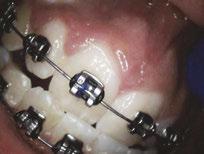

Dr. Bill Waggoner discusses the benefits of using liners along with a case presentation from Dr. Paul Bahn

Cavity liners and indirect pulp capping (IDPC) materials have been used in dentistry for decades. The recent introduction of NuSmile’s NeoLINER™ LC now provides one of the most therapeutic, easy-to-use liners on the market! It is a light-cured MTA-modified bioactive material that is recommended for use as either a cavity liner or as an indirect pulp-capping material. For decades, calcium hydroxide was the most popular lining or indirect pulp-capping material, primarily because of its ability to stimulate reparative dentin. However, its solubility after placement was found to be a problem. Zinc oxide and eugenol, glass ionomers, and resin-modified glass ionomers have also been used as liners, bases, and IDPC materials, but each has shortcomings.

Liners are materials that are placed in thin layers over exposed dentin in the deepest portion of cavity preparations. They function to seal dentin tubules, prevent microleakage, provide some thermal insulation, and depending on the material used, stimulate the formation of reparative or tertiary dentin. Historically, indirect pulp-capping materials have been used when a thin layer of carious dentin remains after deep excavation with no exposure of the pulp and no clinical signs of irreversible pulpitis. In recent years, indirect pulp capping in pediatric dentistry has been utilized when larger amounts of carious tissue remain, but the caries can be sufficiently sealed from the oral environment with a full coverage restoration like a stainless steel or zirconia crown. The main goal of both liners and IDPC materials is to minimize inflammation, promote healing, and maintain vitality of the dental pulp. Indirect pulp capping materials may also demonstrate some bactericidal properties to kill any remaining bacteria that may remain.

The MTA in NuSmile’s NeoLINER LC provides a continuous high calcium release. This, in combination with a high pH, promotes hydroxyapatite formation and protects against hypersensitivity. The high pH also has bactericidal effects to reduce remaining bacteria. NeoLINER LC is packaged in a syringe with 27-gauge disposable tips that allow for precise and easy placement. Its viscosity ensures it will stay in the area where it is placed until it is cured with a curing light. NeoLINER LC is

moisture tolerant, has low water solubility, and is compatible with all etching, bonding, and resin restorative materials. It’s also radiopaque for easy postoperative assessment.

While it is an excellent liner and IDPC material, NeoLINER LC is not recommended for direct pulp capping because of its resin component which can act as an irritant. Any materials containing a resin can damage or kill pulpal tissue if placed in direct contact. If a pulpal exposure is realized, a resin-free MTA material such as NuSmile’s NeoMTA® 2 or NeoPUTTY® is recommended as a direct pulp-capping agent due to its exceptional biocompatibility. These MTA materials, which have a delayed set, may be covered with NeoLINER LC for placement of an immediate final restoration.

Figure 1: Preoperative periapical radiograph of tooth No. 30 with a large radiolucent lesion approximating the distal pulpal horn and a smaller radiolucent lesion closer to the mesial marginal ridge Figure 3: Conservative removal of all carious dentin on all axial walls and pulpal floor. No clinical pulpal exposure noted, but likely very close to distal buccal pulp horn Figure 2: Large active carious lesion involving the entire distal buccal cusp and surrounding aspect of tooth No. 30. Smaller Class VI lesion located on the mesial lingual cusp on No. 30 Figure 4: Placement and curing of two separate thin layers of NeoLINER over the dentin. Image depicts the NeoLINER following the indirect pulp cap of tooth No. 30